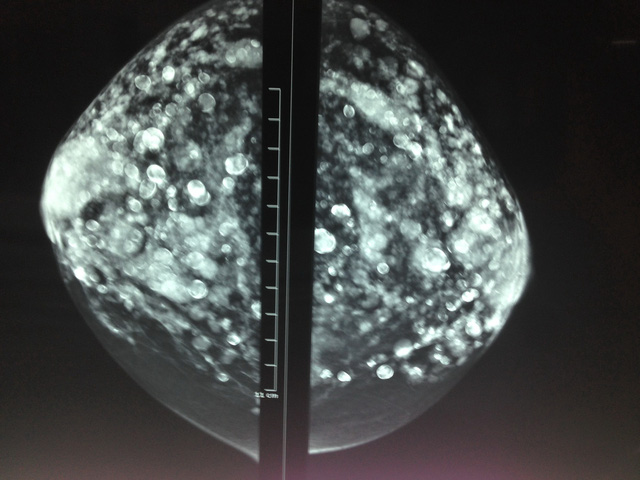

Hình ảnh silicon "nở ngàn bong bóng" trong bầu vú bệnh nhân - Ảnh: Bác sĩ Phan Thanh Hải cung cấp

Ngày 28/10, bác sĩ Phan Thanh Hải - giám đốc phòng khám đa khoa Hòa Hảo - cho biết bệnh nhân là bà H.T.H.T (67 tuổi, quê Đồng Tháp) đến phòng khám đa khoa Hòa Hảo chụp nhũ ảnh ngày 24-10 do có bất thường ở cả hai vú.

Kết quả chụp xquang phổi thấy hình ảnh bất thường như là di căn ung thư phổi, còn hình chụp nhũ ảnh hai bên vú lại đầy các bong bóng tròn, nhỏ ở khắp nơi.